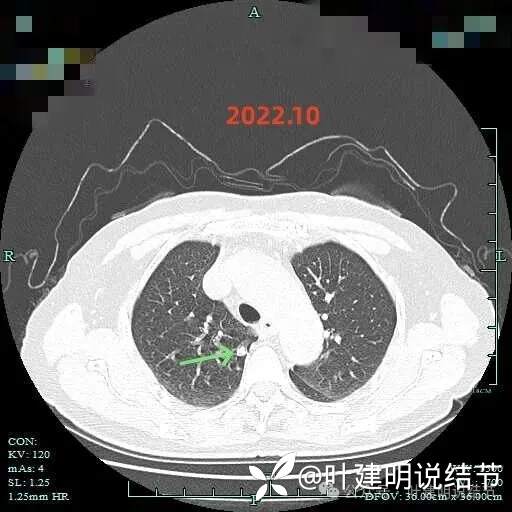

病灶出现,有磨玻璃成分,有血管进入与穿行,血管略有增粗。

混合密度,实性成分明显,微小血管进入明显,整体轮廓清楚,瘤肺边界清楚。

边缘有少许毛刺,实性部分密度较高,牵拉胸膜,边缘少许磨玻璃成分。

边缘区域有磨玻璃成分,实性部分密度主,紧贴胸膜。

边缘淡磨,血管走向病灶。